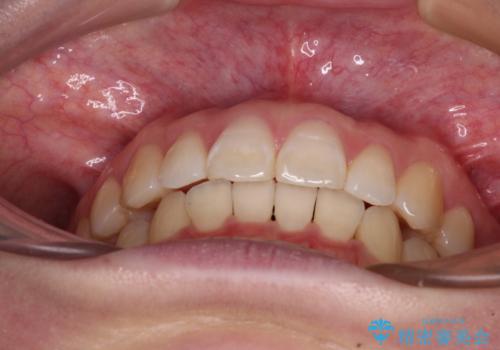

- 上顎前歯の隙間を気にして来院された患者様です。

下顎前歯が上顎前歯に食い込むような咬み合わせにより、上顎前歯が開いてしまっていたため、咬合高径の挙上により突き上げを改善するよう、インビザラインにより矯正治療を行うこととしました。

咬合高径の挙上により上顎前歯の突出感も改善することができ、整った口元となりました。